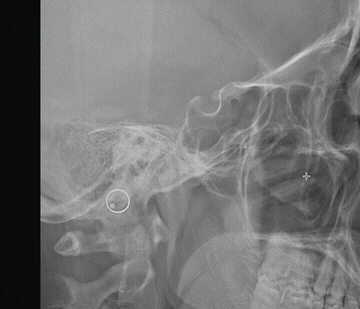

ROI brush painting

Paint cranial base ROI